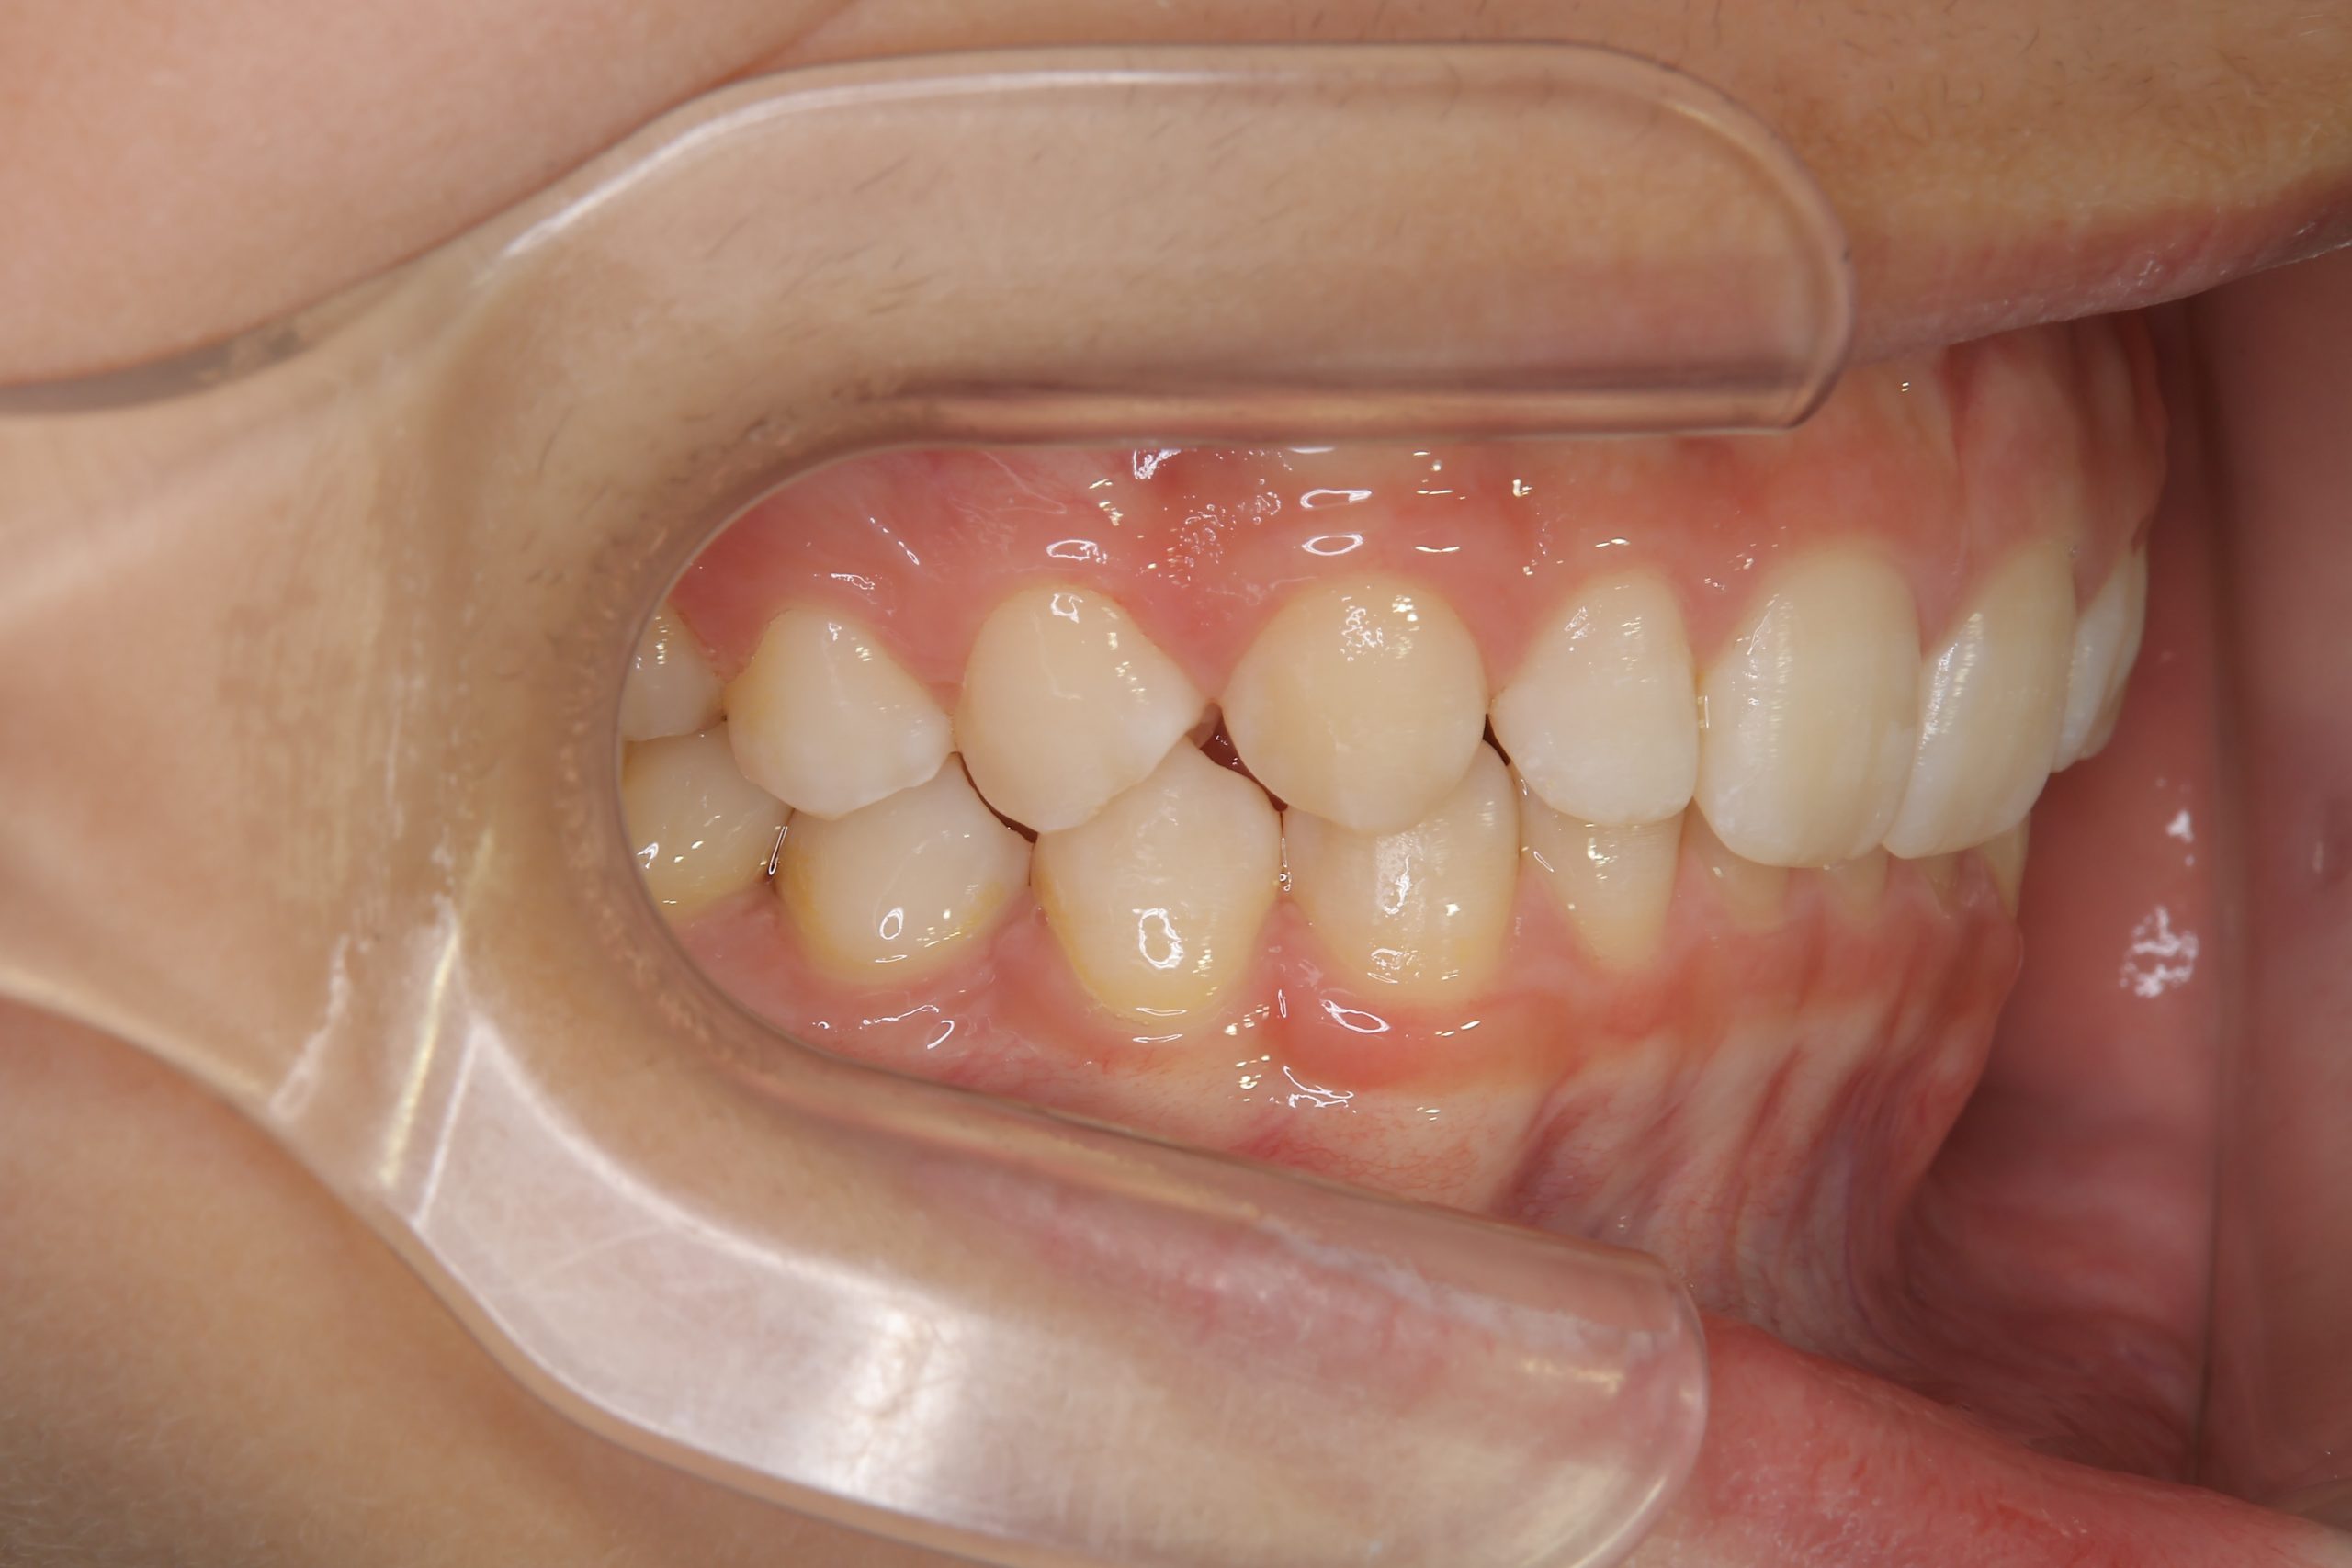

ビフォー

子どもの矯正治療|症例_121

主訴 歯並び

施術内容 上顎急速拡大装置と下顎リンガルアーチを用いて上下顎骨を拡大した。

その後マウスピース型矯正装置で歯牙を配列し良好な咬合を獲得した。

治癒期間 3年11ヶ月間